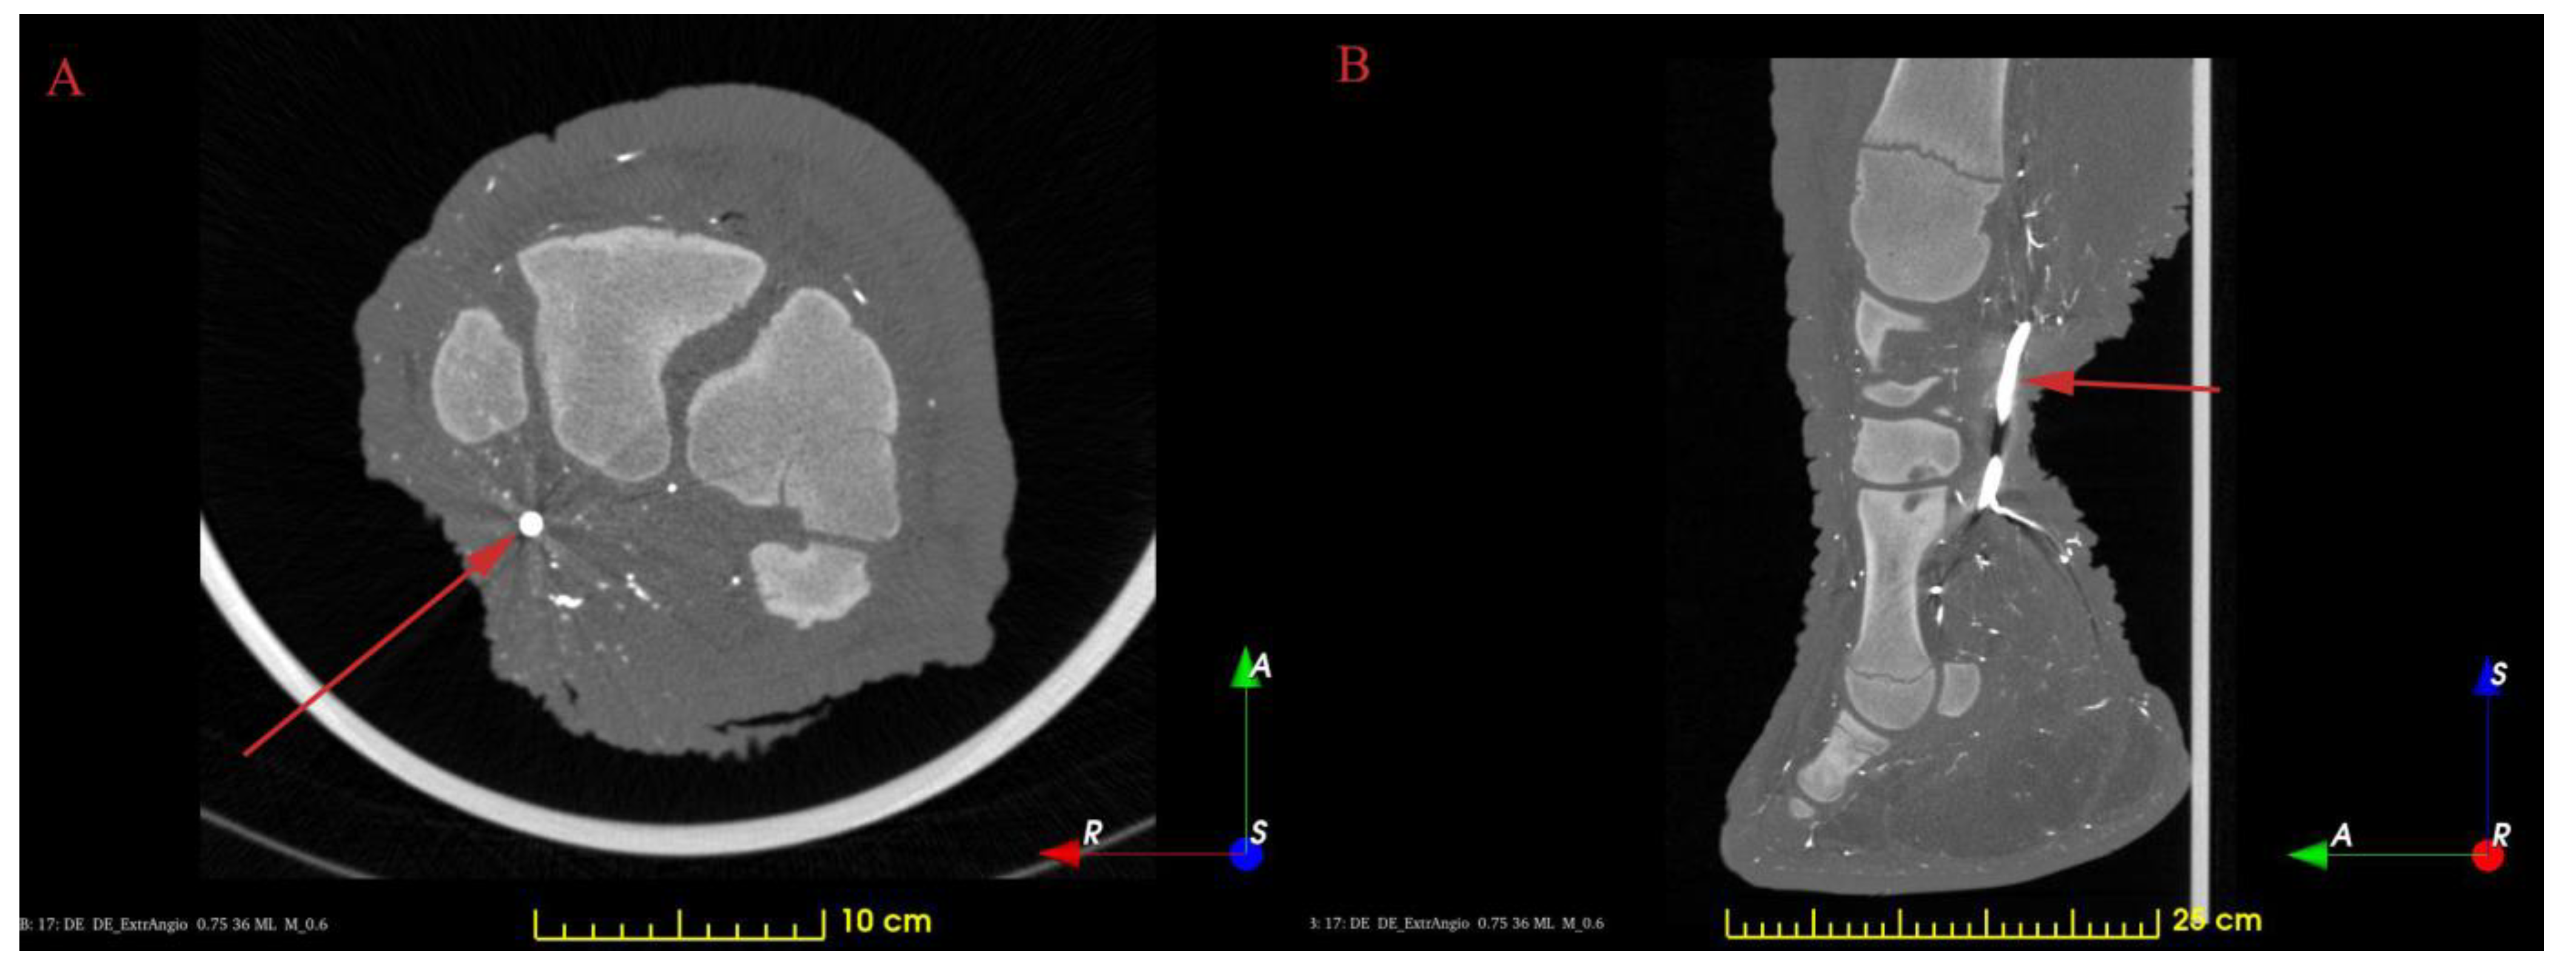

3. Results and Discussion

3.1. The Skeleton of the Forefoot

3.2. Results of the Vessel Reconstructions